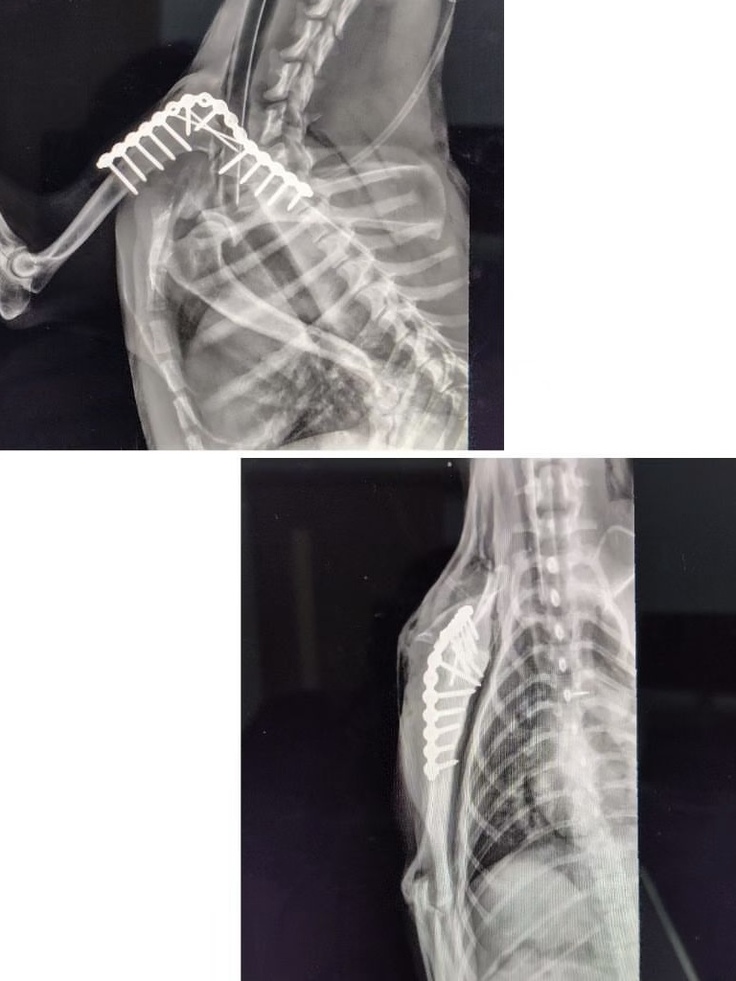

手術でプレート固定を勧められました。回復率は85%程度。費用はいくらかかるんだろう。でも、やってみて良くなる可能性があるのであれば、手術をしていただこう、という決断になりました。

(この後、レントゲン写真や術後の患部の写真があります。苦手な方は避けてください)

詳しくはわからない素人ながら、うまく手当てをしていただいたのだろう、と思います。お見舞いに行ってもみましたが、喜んで跳ね回るのが心配でもあり。